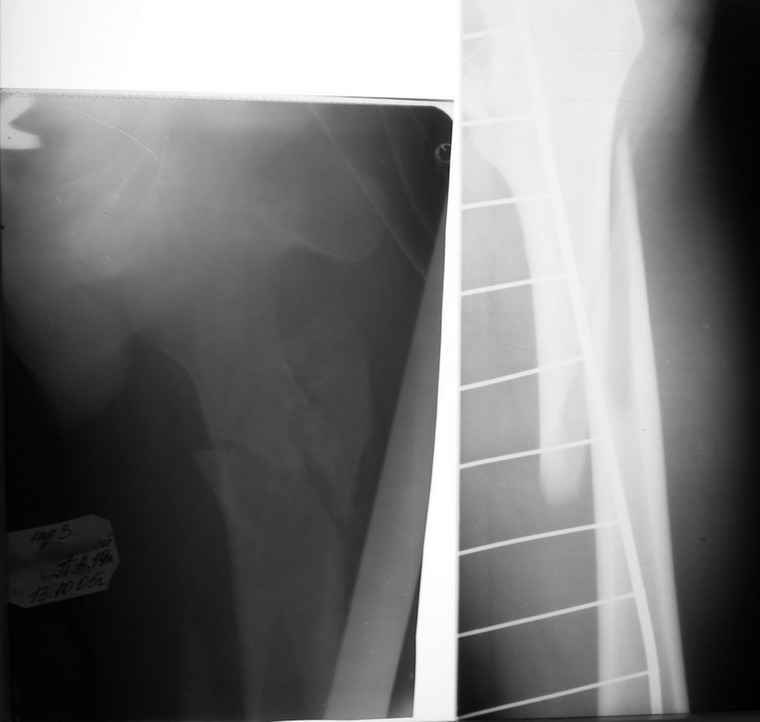

Вот снимки по свежей ситуации, парень 19 лет, длинный оскольчатый перелом бедра от шейки до в-с/3. давно уже ходит на своих ногах.

Делалось не мной (ассистировал), я на тазах "пока ещё не волшебник, а только учусь"

Представленные Вами рентгенограммы действительно являются примером качественной фиксации спице-стержневым аппаратом. Они, как ни что другое, многое иллюстрируют.

Кроме того, было бы ошибкой ставить знак равенства между нашим и Вашим пациентами. Они не только не похожи, разница между ними просто огромная. Говорю это не для того, чтобы задеть Вас или обидеть. Ни в коем случае. Просто теперь я понимаю, что Ваше мнением строится на простом преломлении Ваших подходов к лечению пациентов со свежими переломами, на ситуацию, абсолютно несопоставимую, подобную нашей.

Компоновку данного аппарата, в котором дистальный отломок фиксирован лишь на дистальном уровне, а проксимальный вообще сам по себе никак, только через бывший сустав, назвать стабильной никак нельзя. Нет стабильности - нет нормального заживления, но есть осложнения, надеюсь, это-то можно экстраполировать на вашего больного?